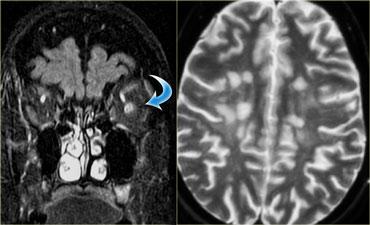

Trên hình bên trái, thần kinh thị giác bên phải có hình ảnh bình thường.

Lưu ý rằng thần kinh thị giác là một bó chất trắng.

Nó có cùng cường độ tín hiệu với chất trắng trong não.

Ở phía đối bên, thần kinh thị giác có tín hiệu tăng cao.

Đây là tổn thương ngoài nhãn cầu trong nón cơ, và chúng ta cần nghĩ đến các bệnh lý tân sinh so với bệnh lý mất myelin.

Tiếp tục xem hình ảnh tiếp theo.Bên trái là hình ảnh chuỗi xung FLAIR kết hợp kỹ thuật ức chế mỡ (fat-sat).

Lưu ý tín hiệu bất thường và thực tế là thần kinh thị giác không bị phì đại, điều này giúp loại trừ khả năng u.Hình ảnh tủy sống cổ cho thấy một đoạn dài tổn thương không chiếm chỗ.

Dựa trên các hình ảnh này, chẩn đoán phân biệt bao gồm xơ cứng rải rác (MS) và hội chứng Devic (còn gọi là viêm tủy thị thần kinh).

Do MS phổ biến hơn nhiều, đây sẽ là chẩn đoán có khả năng nhất, nhưng trường hợp này thực tế là hội chứng Devic.Một số tác giả coi hội chứng Devic là một thể của MS, tuy nhiên hội chứng Devic khác với MS ở các điểm sau:

Bên trái là hình ảnh của một bệnh nhân khác, cũng có viêm thần kinh thị giác.

Có tín hiệu tăng trong thần kinh thị giác và trong não có nhiều tổn thương là hậu quả của MS.

Các tổn thương này không xuất hiện cùng một thời điểm, do đó có sự phân tán theo thời gian và không gian, đây là đặc điểm đặc trưng của MS.-